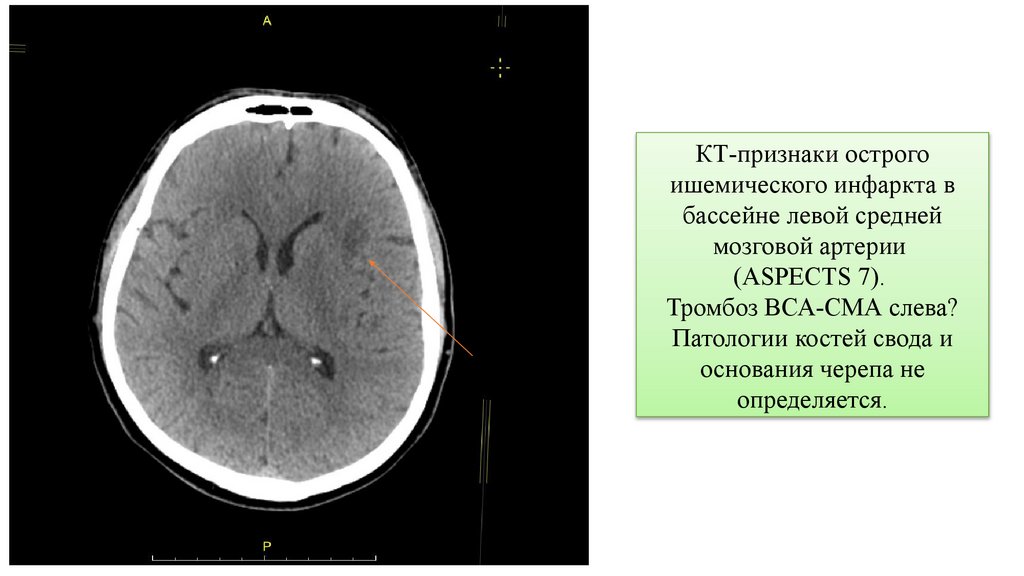

КТ-признаки острого

ишемического инфаркта в

бассейне левой средней

мозговой артерии

(ASPECTS 7).

Тромбоз ВСА-СМА слева?

Патологии костей свода и

основания черепа не

определяется.